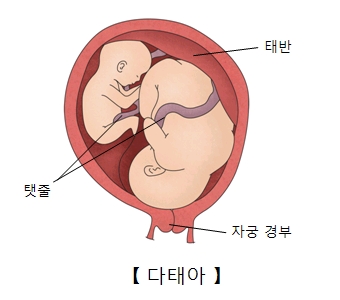

다태아(Multifetal pregnancy)

다태아는 둘 이상의 태아가 동시에 임신이 되는 상태를 의미합니다. 쌍둥이, 세쌍둥이, 네쌍둥이 등을 말합니다.

겉모습으로 볼 때 임신 주수에 비해 산모의 배가 클 경우 다태아를 의심합니다. 초음파상으로 태아가 한 명 이상인 것을 확인하면 다태아를 확진합니다.

특히 일란성 쌍태 임신에서는 두 태아 사이의 혈관 문합을 통한 혈류의 불균형으로 인한 합병증이 발생할 위험이 있습니다. 태아의 기형이 발생하는 빈도도 더 높습니다. 따라서 16주 이후부터는 2주 간격으로 초음파 검사를 시행해야 합니다.

다태아를 임신한 여성은 뱃속 아기의 수에 비례해 합병증이 생길 확률이 높아집니다. 태반이나 양막의 모양에 따라서 다태아의 합병증이 달라질 수 있습니다. 여러 합병증이 동시에 발생할 수도 있습니다. 혈압 상승, 부종, 단백뇨 등의 증세가 동반되는 자간전증이 발생하기도 합니다. 이는 생명을 위협하는 매우 위험한 합병증입니다. 쌍둥이를 임신한 여성은 단태아를 임신한 여성보다 자간전증을 일으킬 확률이 2배 더 높습니다. 이외에 갑작스러운 체중 증가, 두통, 현기증, 임신 제2기와 제3기 때의 메스꺼움, 구토, 통증, 손발과 얼굴의 부기와 같은 합병증도 있습니다.